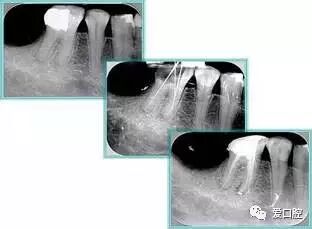

如图为塑化加根充处理后牙齿 X 线片▼

牙胶尖什么颜色最全整理 | 根管治疗标准步骤和细节把握_https://www.jmylbn.com_新闻资讯_第33张

常见有修复性钙化和增龄性钙化。下面为根管钙化 X 线片。

牙胶尖什么颜色最全整理 | 根管治疗标准步骤和细节把握_https://www.jmylbn.com_新闻资讯_第35张

右图及下图为器械折断的 X 线片。箭头处示折断器械

牙胶尖什么颜色最全整理 | 根管治疗标准步骤和细节把握_https://www.jmylbn.com_新闻资讯_第36张

右图箭头处示台阶形成

牙胶尖什么颜色最全整理 | 根管治疗标准步骤和细节把握_https://www.jmylbn.com_新闻资讯_第37张